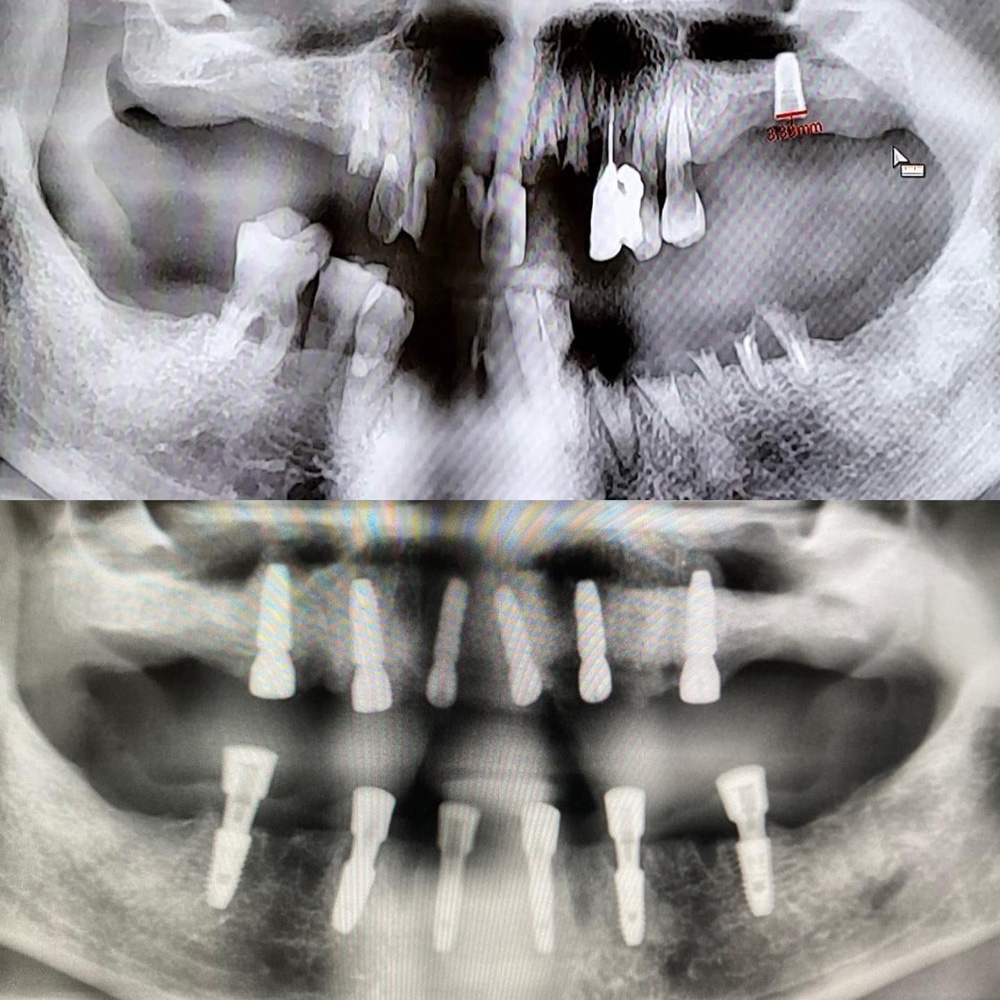

一天 是全口咬合功能及美觀徹底改善需要的時間

全口重建(All on 4/6) 案例